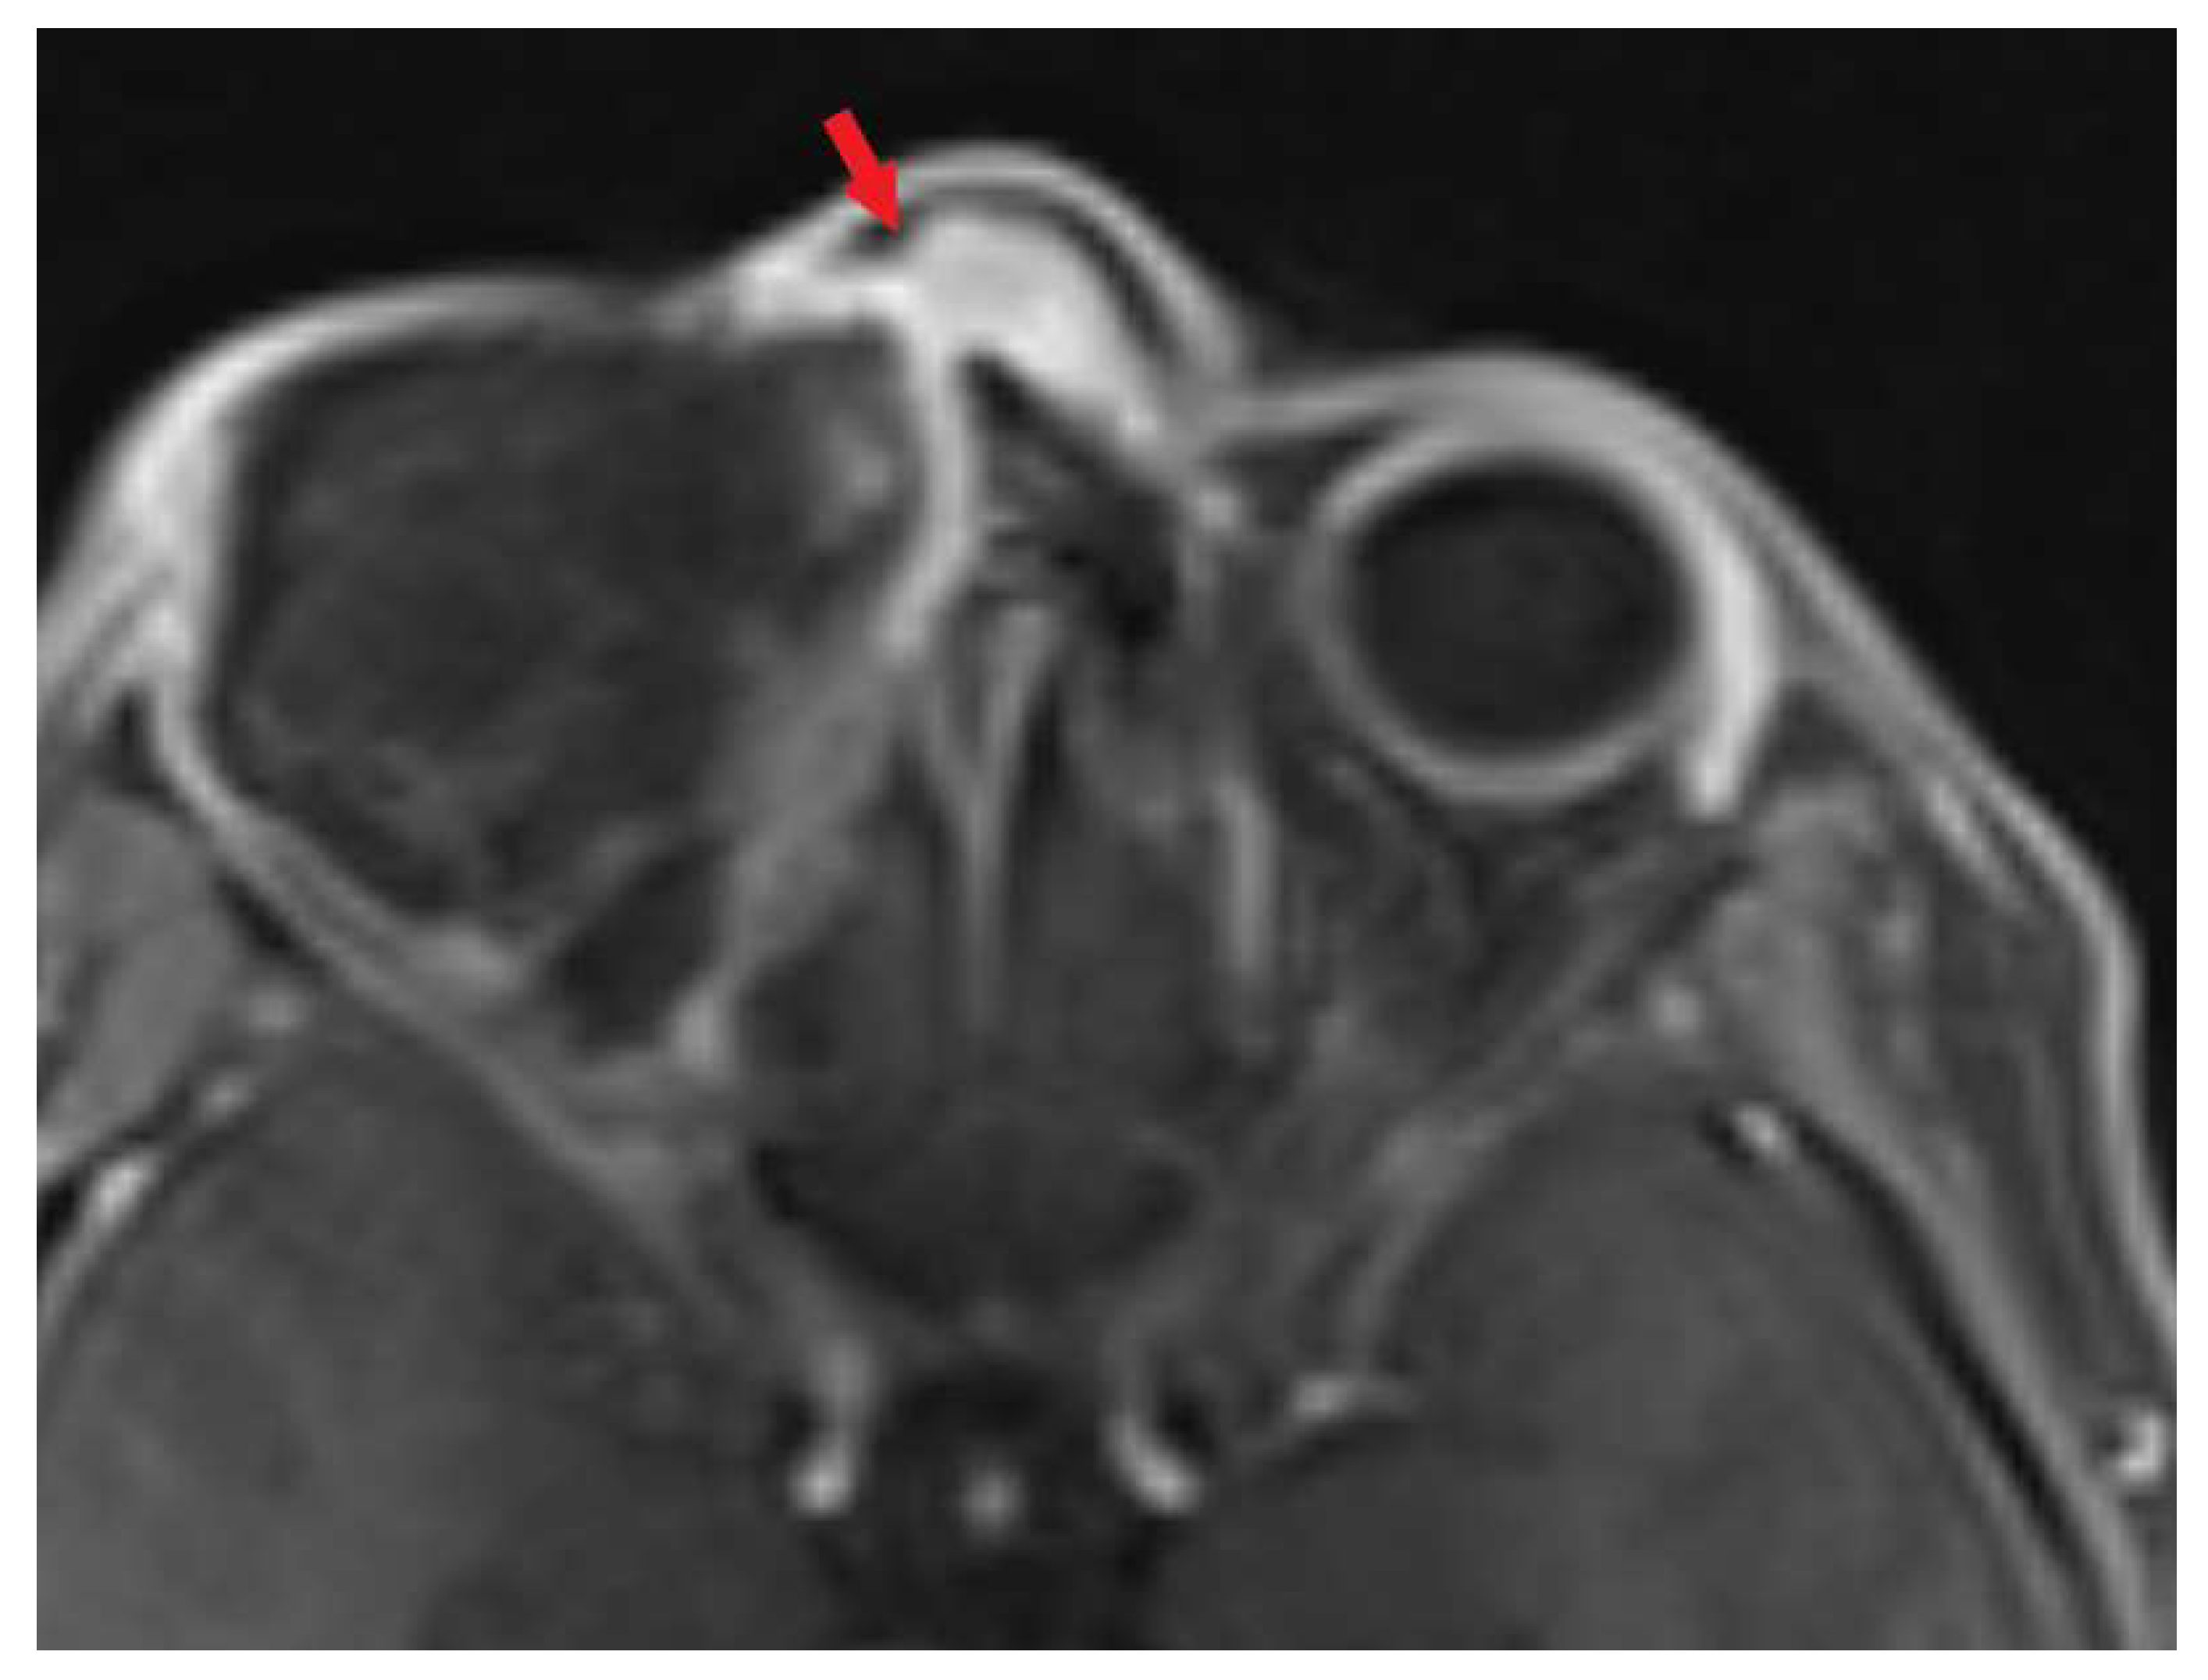

2. Case Presentation